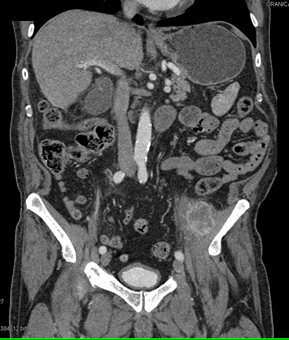

In this patient the best diagnosis for the left hip pain is?

CTisus Quiz   CTisus Quiz

metastatic renal cell carcinoma to muscle

primary sarcoma

lymphoma

abscess